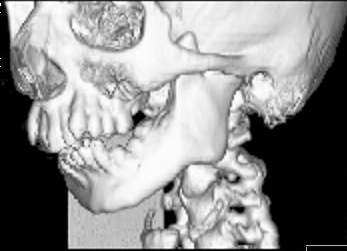

Пациент В., 13 лет. Диагноз: Костный анкилоз левого височно-нижнечелюстного сустава (ВНЧС), левосторонняя микрогения. Болеет с 2-х летнего возраста. Возможная причина развития анкилоза – воспалительный процесс (в первые 1,5 года жизни часто болел простудными заболеваниями, травму родители отрицают). В 3 и 5 лет проводилась редрессация – безуспешно. Прилагаются: ортопантомограмма, кадры СКТ с 3Д реконструкцией. Вопросы: определение тактики лечения – вид и сроки реконструктивно-пластической операции (этапов операции), а именно – неоартропластики и устранения микрогении, медикаментозная терапия в до- и послеоперационный период, ортодонтическое лечение.